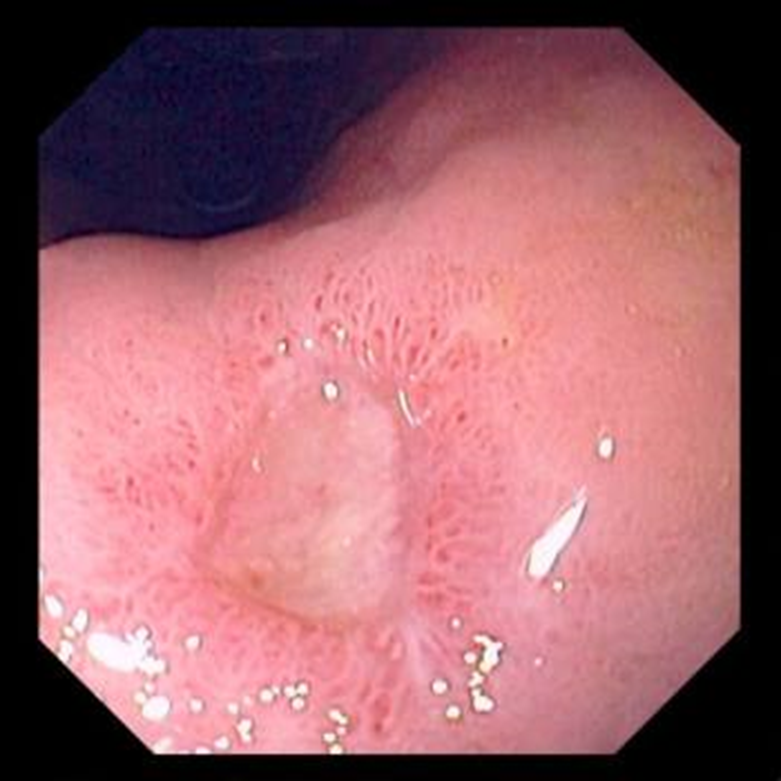

Loét dạ dày

image 1

Chẩn đoán loét đường tiêu hóa được nghĩ đến dựa vào tiền sử của bệnh nhân và được xác nhận bằng nội soi. Điều trị theo kinh nghiệm thường tiến hành mà không có chẩn đoán chính xác. Tuy nhiên, nội soi cho phép sinh thiết hoặc thu mẫu tế bào học của các tổn thương dạ dày và thực quản nhằm phân biệt giữa bệnh loét đơn thuần và ung thư dạ dày thể loét. Ung thư dạ dày có thể biểu hiện với các triệu chứng tương tự và phải được chú ý loại trừ, đặc biệt ở những bệnh nhân > 45 tuổi, sút cân, có các triệu chứng nặng hoặc dai dẳng. Tỉ lệ loét tá tràng ác tính rất thấp, do đó sinh thiết tổn thương tá tràng thường không cần thiết. Nội soi cũng có thể được sử dụng để chẩn đoán xác định nhiễm H. pylori, điều này cần làm khi phát hiện thấy vết loét.